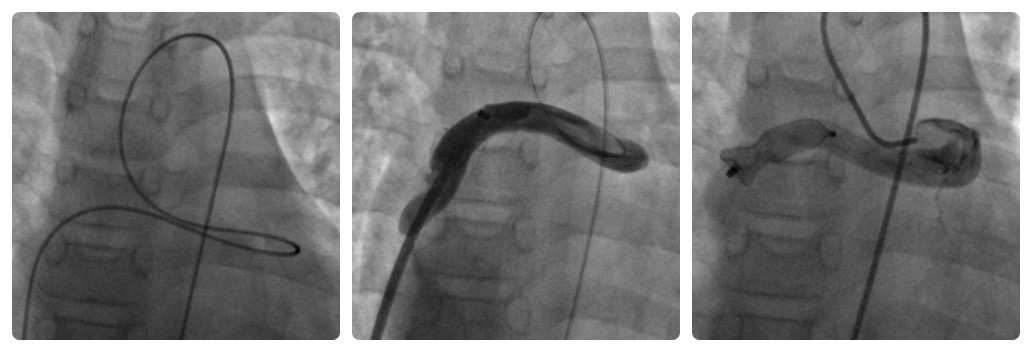

Через артериальным доступом проведен проводник Wishper 0.014" через фистулу в правое предсердие и НПВ, выполнен захват проводника ловушкой типа «лаcсо», проводник выведен через венозный доступ, таким образом сформирована артериовенозная петля. Венозным доступом по коронарному проводнику проведено доставочное устройство SFP8 Fr, по которому в фистулу доставлен PDA окклюдер «LifeTech» XJFD 1012.Окклюдер расположен в полости фистулы, проксимальнее деления фистулы на стволы, таким образом закрыт весь просвет фистулы. Контрольная ангиография показала минимальный сброс контраста через тело окклюдера. Давление в ПЖ 30/4 торр. Осложнений во время процедуры не было. Время операции 35 мин, рентгеноскопии 12 мин. (рис. 2).

Рис. 2: А) Сформирована «артериовенозная петля» для проведения системы доставки чрезвенозным доступом; B) доставочное устройство установлено в КФ; С) контрольная ангиография, PDA окклюдер полностью закрывает полость КФ.